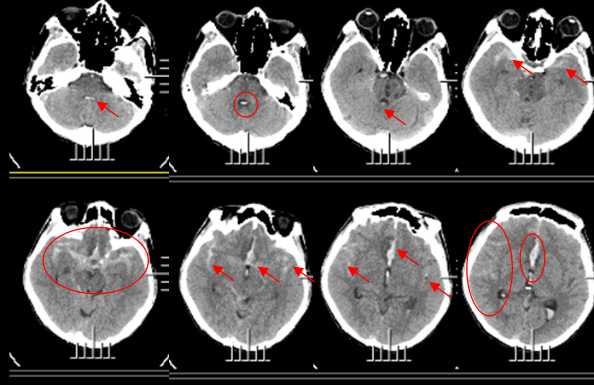

第二例是未破裂动脉瘤,72岁老年女性,脑梗塞入院,入院后行头颅核磁显示右侧大脑前动脉,胼周动脉及胼缘动脉分叉处可疑动脉瘤,后行DSA检查确诊为大脑前动脉,胼周动脉及胼缘动脉分叉处动脉瘤,大小约5mm×4mm×3mm,经与家属沟通决定行介入栓塞治疗。

MRA检查大脑前动脉可疑动脉瘤

术中DSA造影右侧胼周动脉及胼缘动脉分叉处瘤,大小约5mm×4mm×3mm。

介入栓塞术后造影动脉瘤完全不显影

术后第三天患者下地行走,一周后出院。